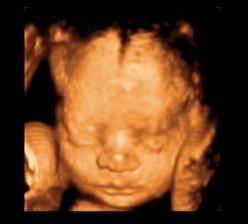

26 tt../1.4.2009/ naša paulínka je stráášne zlatá, boli sme si pozrieť na 4D utz. ..tvárila sa veľmi dôležito, až nafúkano...hehe..vôbec sa nechcela usmievať... nakoniec sa nám aj zasmiala...v brušku veľmi vyvádza, maminke dosť vytláča všetky časti telíčka, čo je niekedy aj dosť bolestivé...ale vydržíme, drobečkovi je tam určite tiež pritesno..a ešte aj stále viac a viac bude... strááášne sa na ňu tešíme🙂))